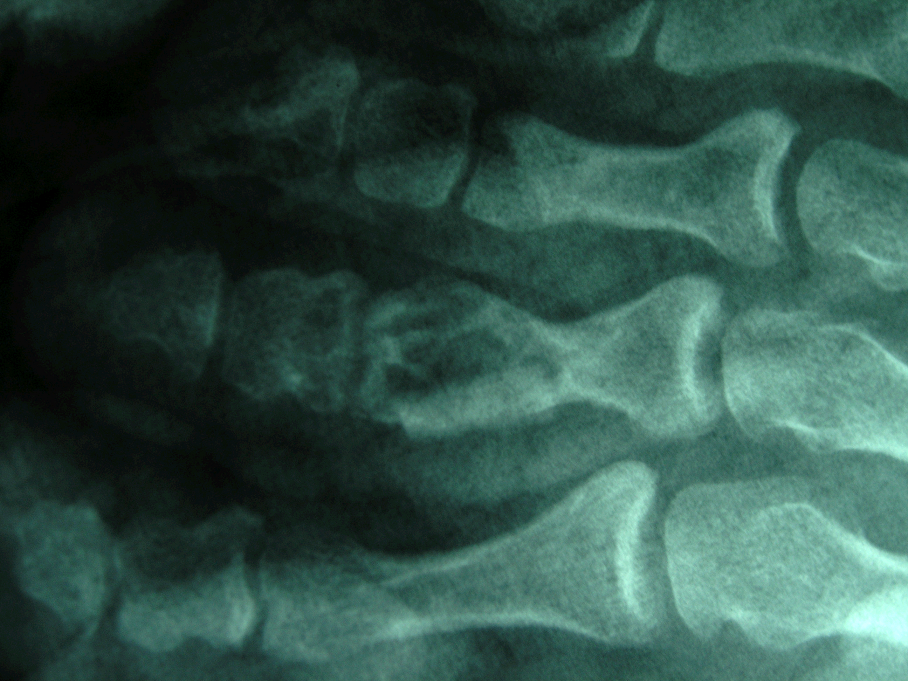

患者,男,30岁,右足第三趾近节腱鞘巨细胞瘤并骨破坏,行肿瘤切刮除及异体骨植骨术。

术后X线片